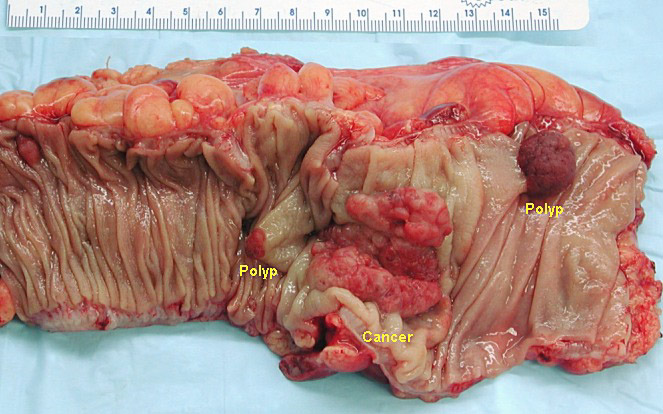

Colon cancer: Colorectal mucosa ranks third for most common site of cancer, and colorectal carcinoma causes the third most cancer-related deaths. The two categories of colon cancer are polypoid and non-polypoid. The subtypes of polyps are listed below:

- Adenomatous - These polyps are pre-malignant lesions arising from the glandular tissue of the colon (adeno-), and can progress to carcinoma. The most common site of metastasis is the liver.